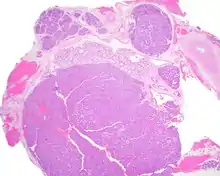

Most patients present in the 7th decade of life, with females affected much more commonly than males (about a 4:1 ratio). The vast majority of the tumors present in the upper lip, although a few present in the palate or buccal (cheek) tissue as a slowly enlarging mass.[3] It is curious that the tumor may show multifocality or multinodularity, a finding that should not be confused with invasion clinically or with malignancy.[1][4]

Tumors are usually small because they come to clinical attention early on in development, with an average size of about 1.6 cm.[1] There is a very characteristic appearance to the tumor when reviewed histologically.